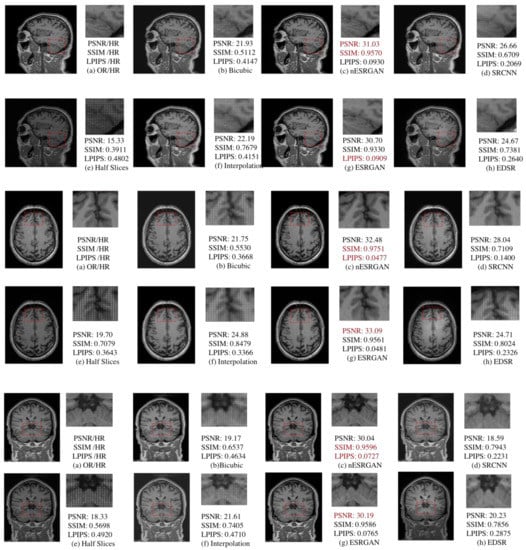

We chose RFB-ESRGAN in order to verify its advantages of high-detail information, and compared it with the traditional super-resolution methods in deep learning (Table 1). We found that RFB-ESRGAN performed best in image evaluation indicators and visual quality overall (Figure 11).

Figure 11.

Comparison of SRCNN [36], FSRCNN [27], EDSR [15], SRGAN [17], ESRGAN [18], RFB-ESRGAN [19] in the first reconstruction.

We tested the slices of three planes in the first super-resolution process, and RFB-ESRGAN was superior to other super-resolution methods according to the image evaluation indicators (PSNR, SSIM, LPIPS). Moreover, in terms of detail, RFB-ESRGAN had more detailed features and the best performance in the three planes. The results are shown in Figure 11.